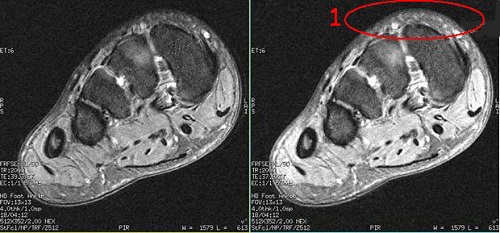

Extreme High Resolution Optimization

Use Extreme High Resolution Optimization to reduce motion artifact for high resolution scanning. The tradeoff is an increase in echo spacing and fine line artifacts.

- The extreme high resolution optimization feature is only active when User CV9 is turned on and the frequency pixel size is ≤ 16 cm/512.

- If your clinicians are concerned about fine line artifact, turn off Extreme High Resolution Optimization.